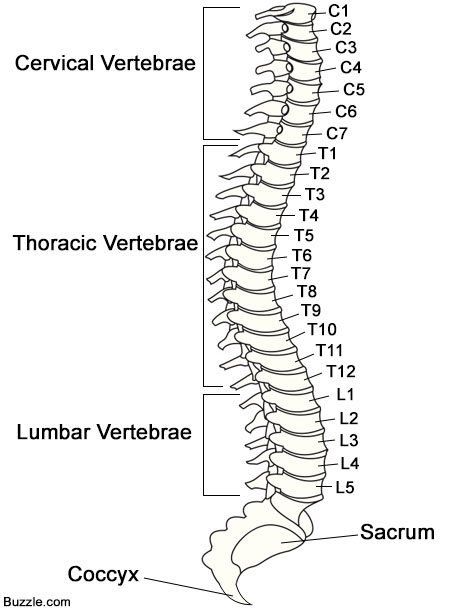

A spinal injury refers to damage to the spinal cord or the bones, tissues, and nerves surrounding it. It can be life-altering, depending on the severity and location of the injury.

Types of Spinal Injuries

- Complete: No sensation or movement below the injury site.

- Incomplete: Some function remains, like partial movement or feeling.

- Paraplegia: Affects the lower body (legs and pelvic organs).

- Tetraplegia (Quadriplegia): Affects all four limbs and the torso.